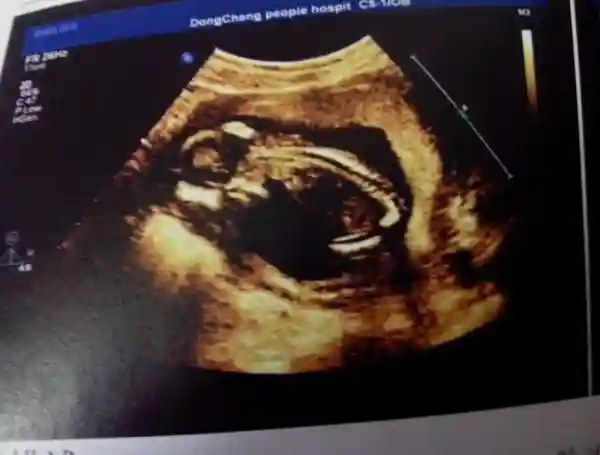

其实与很多人的观念不同的是,在妈妈肚子里的宝宝不是一直只有“睡觉”一件事,他可是很忙的,首先就是忙着保护妈妈的心脏。因为随着孩子的慢慢长大,妈妈会有一种“胸闷”的感觉,这就是因为孩子压迫了妈妈的心脉所导致的。但是另一方面,孩子也“修复”了这些问题,就是用他的胎盘细胞。这样看来,胎宝宝是不是也很暖心呢,小小的他也在下意识的护住孕育自己的母体,这样以确保他和母亲健康的成长。胎宝宝以这样的方式和妈妈共同成长,二者都牵挂着对方,这就是独一无二的血缘。

宝宝在一天天的长大,妈妈的负担也在一天天增多,而随着宝宝一起长大的还有一种干细胞,在保护着宝宝的同时,又在保护着妈妈,这种干细胞可以大大增强妈妈的免疫力。在怀孕的十个月间,妈妈期待着宝宝的到来,宝宝也在默默地陪着妈妈,在妈妈的子宫里干着自己的“小小事业”,就像妈妈呵护着他一般,爱护着妈妈,给妈妈足够的安全感。